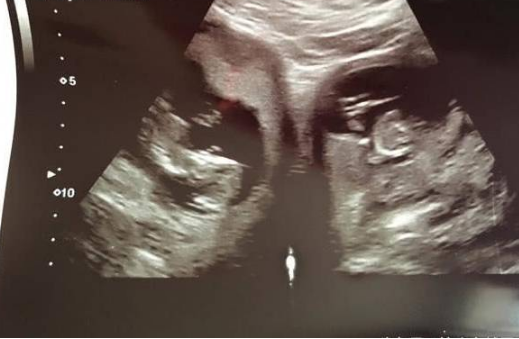

怀了双胞胎对很多夫妇都是惊喜,不过对于英国一位妈妈Jennifer 来说,惊讶的成分更多。原因就在于医生发现她竟然有两个子宫,而且同时受孕。类似的例子全球仅不到100人。

据了解,在做产检的时候,医生发现了Jennifer 拥有双角子宫,而且一侧各住一个宝宝。其实31岁的她已经有了个8岁的女儿,但是当初怀孕的时候却没有发现。Jennifer说道:“我之前有过一个孩子,那时很普通,但这次检查结果出来让我感到相当惊讶。我们是在怀孕第20周照超声波时发现的,从那时起,大家便不断告诉我这有多特别。”

Jennifer和老公Andrew 从去年12月就已经知道是怀了双胞胎,但今年2月才发现她有两个子宫,而且两边都有胎儿。医生表示,这种情况并不会引起额外的问题,但流产或早产的风险会提高。

Jennifer 怀孕34周后,剖腹产下一对龙凤胎。虽然双胞胎刚出生就有黄疸,不过接受两周治疗后便顺利返家。